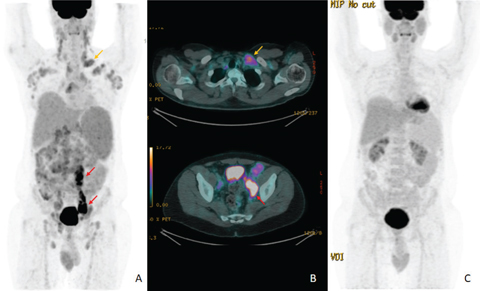

Based on the recent Lugano consensus recommendations for lymphoma staging, PET/CT in Ukraine is recommended as the “gold standard” for DLBCL patients staging and post-treatment assessment, with the following warning: PET/CT at baseline is “recommended”, but not “necessarily required’ in the absence of financial and technical support. For an interim assessment, we would rather provide CT scan, but iPET/CT imaging could be offered to the patient after 3–4 cycles of therapy in case of suspected disease progression. However, in some difficult clinical cases, an individualized approach outside guideline recommendations is required. For example, PET/CT is not recommended during follow-up, but it could be provided in the suspect of an impending relapse when a specific site of disease could be visualized only by PET/CT scan. An example of a patient with DLBCL treated with RCHOPx6 performing PET at different timepoints of the treatment––at baseline, after 2, and after 6 RCHOP cycles––is given in Figure 2.

Fig 2

Figure 2. An example of DLBCL lymphoma with PET/CT scan. San performed at baseline (left), after 2 (center), and after 6 R-CHOP cycles, at the end of therapy (right). The uptake in the mesenteric lesions decreased greatly after 2 cycles (while the CT lesion, not shown, had only a small variation) with an uptake comparable to the liver (complete metabolic response with a Deauville score 3) and substantially disappear after 6 cycles (complete metabolic response with a Deauville score 1).